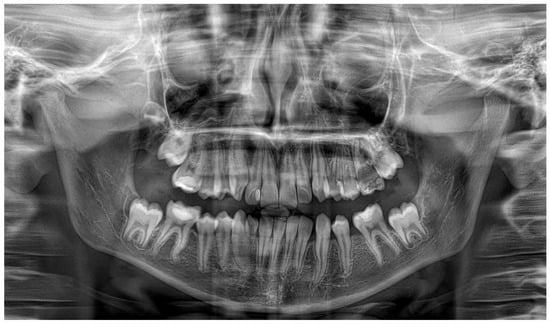

Three months later, the postoperative radiograph showed significant regression of the lesions in the maxilla and mandible, respectively. In addition, the maxillary canine was more extruded, and the mandibular canine and first premolar were more vertically positioned [Figure 2].

Figure 2. Three-month postoperative panoramic radiograph showing a significant reduction of the lesions. The decompression tubes were removed.

One year after decompression, all the permanent teeth involved in the processes erupted, preserving pulpal vitality. The decompression tube had to be adjusted due to the eruption of the canine. Complete regression of both lesions with bone deposition was observed radiographically [Figure 3], and the left inferior alveolar nerve innervation was preserved. A three-year follow-up panoramic X-ray shows no recurrence of the cystic lesions [Figure 4]. Unfortunately, the cavity caused severe destruction of the left permanent first molar.

Figure 3. Twelve-month postoperative panoramic radiograph showing the spontaneous eruption of left maxillary canine and mandibular left canine and first premolar with resolution of both lesions.

Figure 4. A three-year follow-up panoramic radiograph showing full resolution of the pathologies.